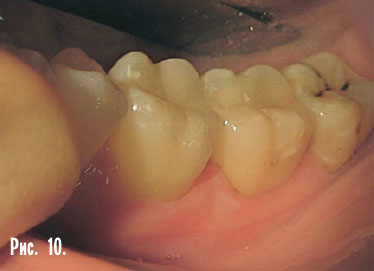

Керамические вкладки (рис. 6–10). Это современная альтернатива фотополимерной пломбе. Фотополимерные пломбы имеют те же недостатки, что и виниры. Так же со временем стареют, покрываются микротрещинами и изменяют свой первоначальный цвет. Фотополимер стирается гораздо быстрее зубов. А для восстановления жевательной поверхности важна прочность и устойчивость к стиранию, этому требованию фотополимерные пломбы не отвечают. Кроме того, пломбы изготавливаются в полости рта пациента, и это не дает тех возможностей, какие есть при работе с моделью. Врач ограничен в пространстве полости рта, не может повернуть зуб во всех направлениях, как модель, и ограничен по времени.